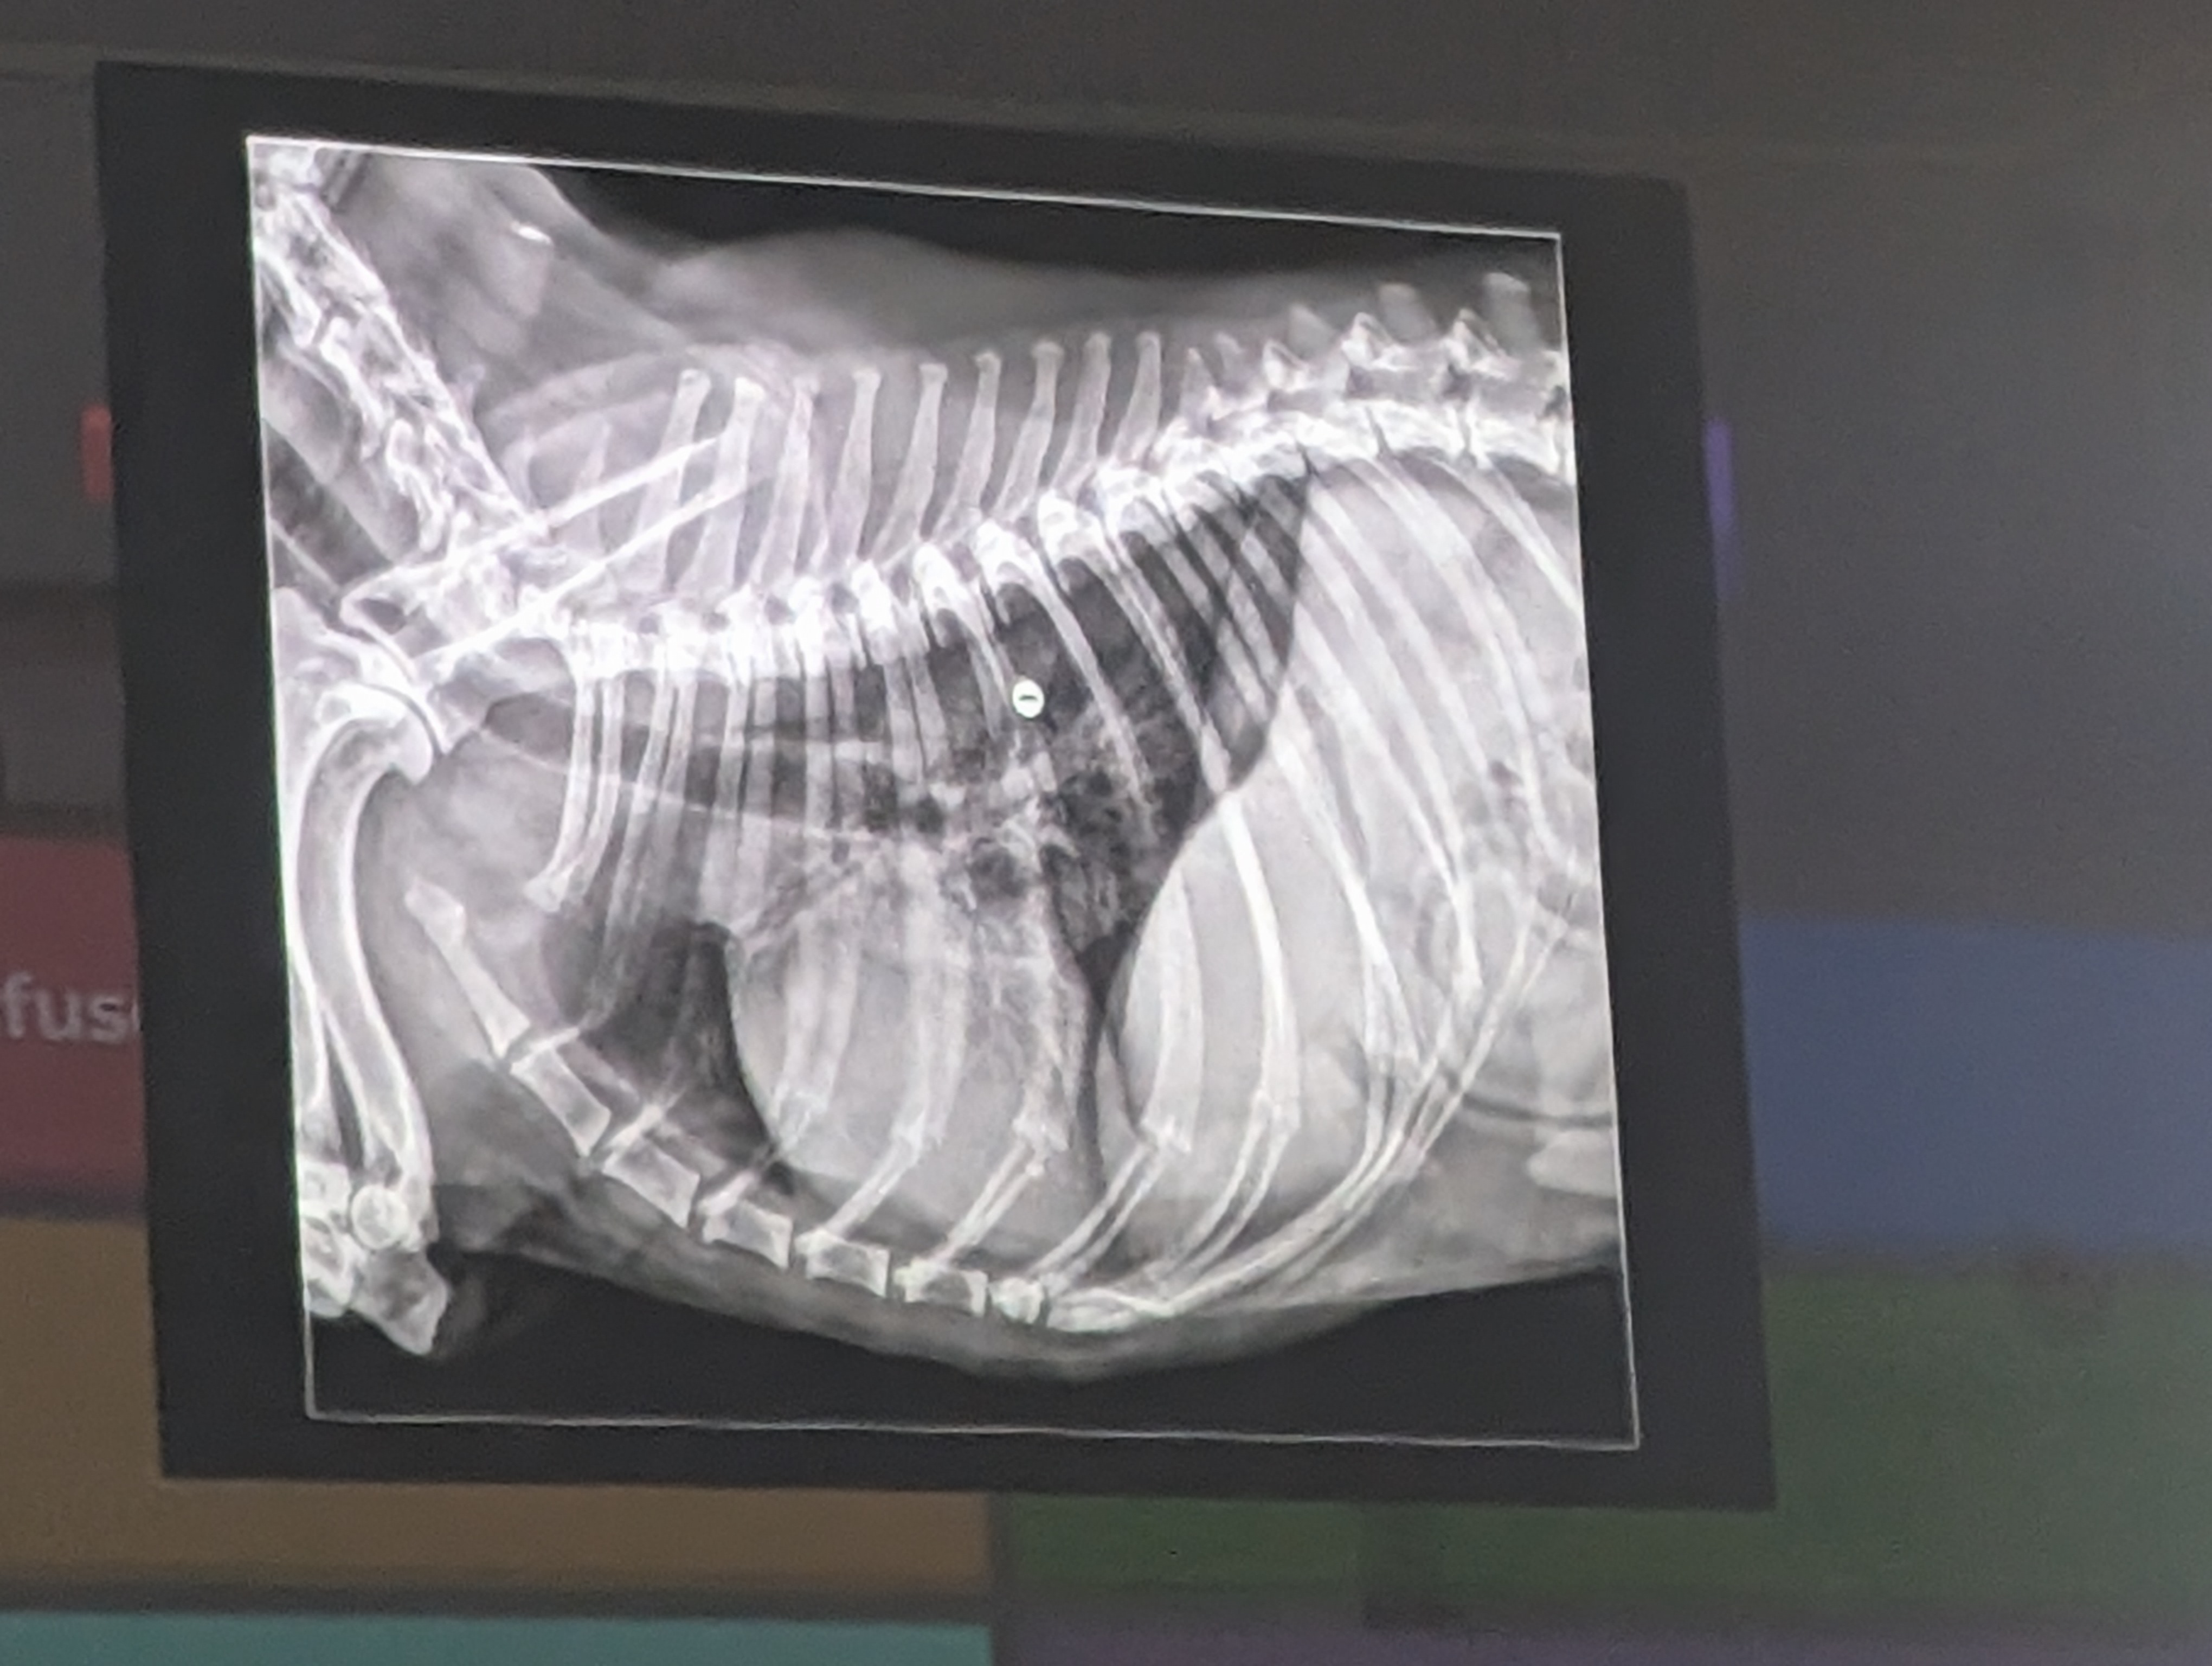

11) Varias respuestas correctas

- Dilatación de la auricula izquierda (Megacardiocefalia)

- Desplazamiento dorsal de la traquea (Por el tamaño del corazón)

- Patrón intersticial difuso (un patrón miliar por todo el pulmon, pero podria ser nodular, reticular o miliar)